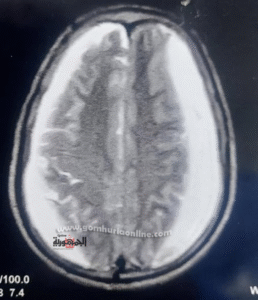

تفريغ ناجح لنزيف دماغي يُنقذ مريضًا سبعينيًا من خطر الموت

كما استقبلت طوارئ المستشفى مريضًا سبعينيًا بسيارة الإسعاف وهو في حالة حرجة ودرجة وعي منخفضة مع ضعف بالجانب الأيمن من الجسم.

أظهرت الأشعة وجود نزيف مزمن تحت الأم الجافية بالمخ، وعلى الفور تم إجراء عملية تفريغ ناجحة، نُقل المريض بعدها إلى العناية المركزة في حالة مستقرة.